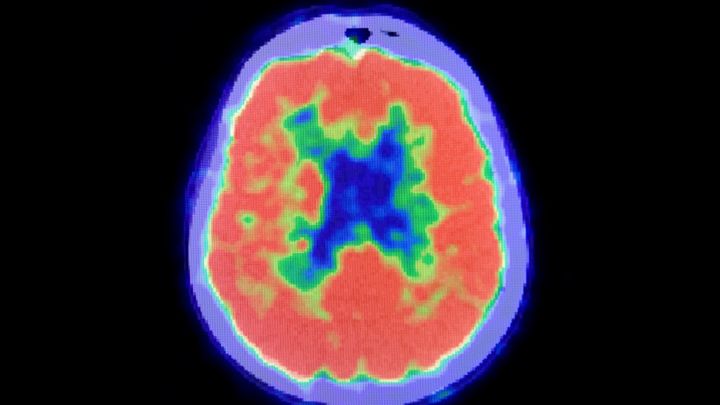

認知機能を評価するための標準的なテスト(ミニメンタルステート検査、モントリオール認知評価)でも、正常値を大きく下回るスコアしか得られず、脳機能がかなり深刻に影響を受けていることが示されました。

これらを踏まえて次に研究者たちは、患者の脳を詳しく検査することにしました。

脳の詳しい検査を行ったところ、脳卒中によって脳の奥深くにある「視床」という部位が損傷を受けていることが明らかになったのです。